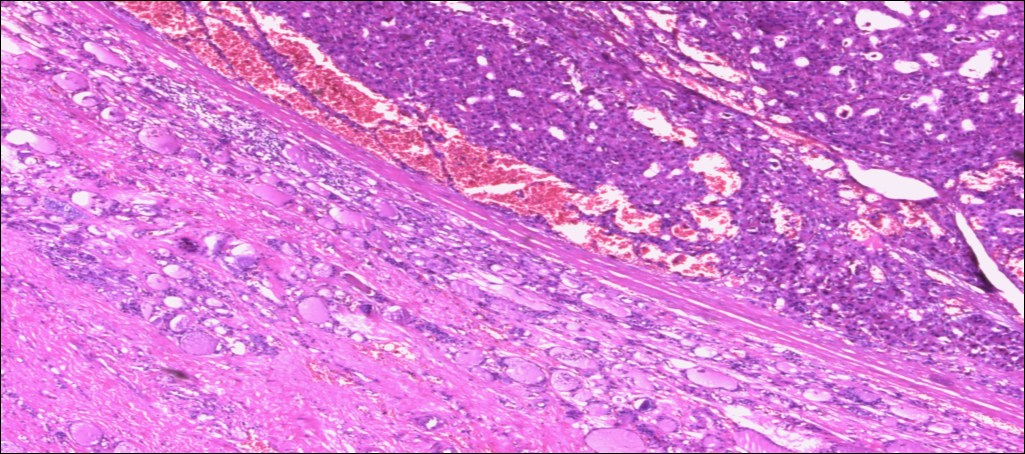

甲状腺嗜酸性细胞腺瘤

(甲状腺右叶及峡部):暗褐结节,直径6cm,包膜完整

肿物包膜完整,镜下未见明确包膜、脉管侵犯

镜下可见包膜,脉管侵犯!